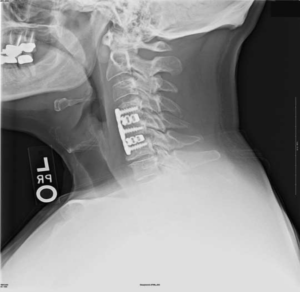

Импланты шейного отдела позвоночника на рентгене.

На шейных уровнях применяются и стабилизирующие тактики оперативных вмешательств, каждая из которых, кстати, может идти совместно и с другими видами операций. Наиболее популярные из стабилизирующих методов:

- - неподвижное соединение (сращивание) двух или более позвонков при их нестабильности;

Если клиника симптомов не поддается консервативной терапии или неинвазивные способы не могут быть задействованными ввиду сильно прогрессирующего стеноза, назначается операция. Вмешательство предполагает использование декомпрессионной ламинэктомии под общим наркозом. При комбинированной проблеме, например, вместе с грыжей, ее сочетают с микродискэктомией и спондилодезом. При спондилодезе осуществляют скрепление смежных позвонков металлическими фиксаторами (стержнями, пластинами, крючками и пр.), установку межтеловых имплантатов или вживление костного трансплантата с металлической гильзой.